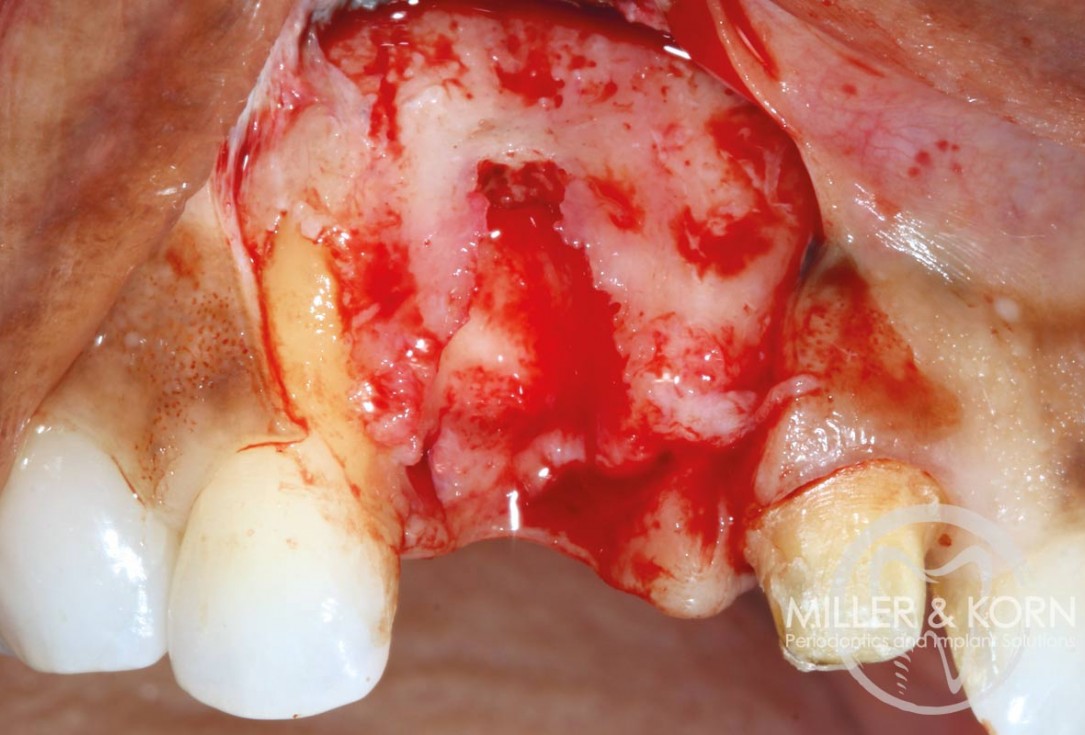

3/22 - Atraumatic extraction of tooth #11Immediate implant placement and regeneration of ridge using an allograft bone ring and Jason® membrane - Drs. Miller and Korn

4/22 - Full thickness flap elevation with vertical releasing incisions. Note, significant apical and buccal bone resorption after raising the flapImmediate implant placement and regeneration of ridge using an allograft bone ring and Jason® membrane - Drs. Miller and Korn